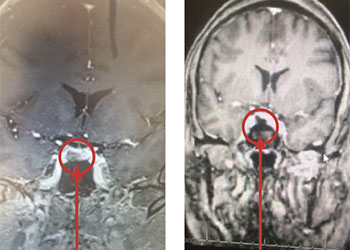

Collateral venous drainage into the orbit and skull base was observed (Figure A). After successful cannulation of the direct aperture between the right carotid artery and […]